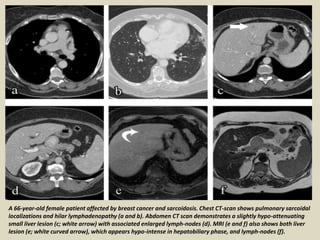

A 66-year-old female patient affected by breast cancer and sarcoidosis. Chest CT-scan shows pulmonary sarcoidal

localizations and hilar lymphadenopathy (a and b). Abdomen CT scan demonstrates a slightly hypo-attenuating

small liver lesion (c; white arrow) with associated enlarged lymph-nodes (d). MRI (e and f) also shows both liver

lesion (e; white curved arrow), which appears hypo-intense in hepatobiliary phase, and lymph-nodes (f).